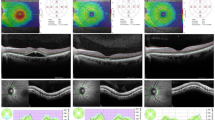

The thicknesses of each retinal layer in RP eyes at different measured points are shown in Fig. 1. The mean thicknesses of each retinal layer in RP eyes and controls are shown in Supplementary Table S1. The thickness of total neural retina of RP eyes was 279.9 ± 41.9 μm which was significantly thinner than that of controls of 330.2 ± 11.8 μm (P < 0.001). The NFL thickness of RP eyes and controls were 41.3 ± 7.1 μm and 27.6 ± 2.1 μm respectively. The GCL thickness of RP eyes and controls were 59.3 ± 9.7 μm and 52.5 ± 2.5 μm respectively. NFL and GCL were significantly thicker in RP eyes than controls (P < 0.001 and P = 0.01 respectively). The IPL thickness of RP eyes and controls were 33.3 ± 4.9 μm and 33.0 ± 2.2 μm respectively and these were not significantly different (P = 0.84). The INL thickness of RP eyes and controls were 50.3 ± 7.2 μm and 44.4 ± 2.3 μm respectively. INL was significantly thicker in RP eyes than controls (P = 0.004). The thickness of outer layers of RP eyes was 95.9 ± 36.5 μm which was significantly thinner than controls of 172.8 ± 7.9 μm (P < 0.001). The visual field scores of RP eyes without CME were 3.6 ± 3.2.

The Spectralis OCT was used to record the cross sectional scans across the retina centered on the fovea (9 mm vertical and horizontal; Fig. 3). One hundred images were averaged with the eye tracking feature to reduce noise and to obtain clearer views of the different retinal layers.

Fundus photograph and optical coherence tomographic (OCT) images of a patient with retinitis pigmentosa (RP).

(A) Representative fundus photograph showing the locations of the 9 mm OCT scans (green lines). Green filled circle indicates the location of the measured points. (B) Representative OCT image. Note that the photoreceptor layer is lost.

In OCT images, the thicknesses of total neural retina, nerve fiver layer (NFL), ganglion cell layer (GCL), inner plexiform layer (IPL), inner nuclear layer (INL) and outer layers were manually measured. The measurements were made at 1 and 2 mm superior, inferior, nasal and temporal to the fovea in the vertical and horizontal images using the built-in caliper function in the Spectralis OCT (version 5.3; Heidelberg Engineering, Heidelberg, Germany; Fig. 4). The mean thicknesses of each layer at these 8 points were used for the statistical analyses. Foveal thickness was also measured in both the horizontal and vertical images and the mean thickness was calculated. The thicknesses of each layer were not measured in RP eyes with CME because it was difficult to make accurate measurements due to the cysts and deformation of the layers. The measurements were performed blind to the clinical information including age, sex or aqueous flare value.

Comparison of each retinal layer thickness between eyes with retinitis pigmentosa and controls.

Magnified image of the white square in Fig. 3 and corresponding area of normal control. The thickness of each layer was measured and compared.